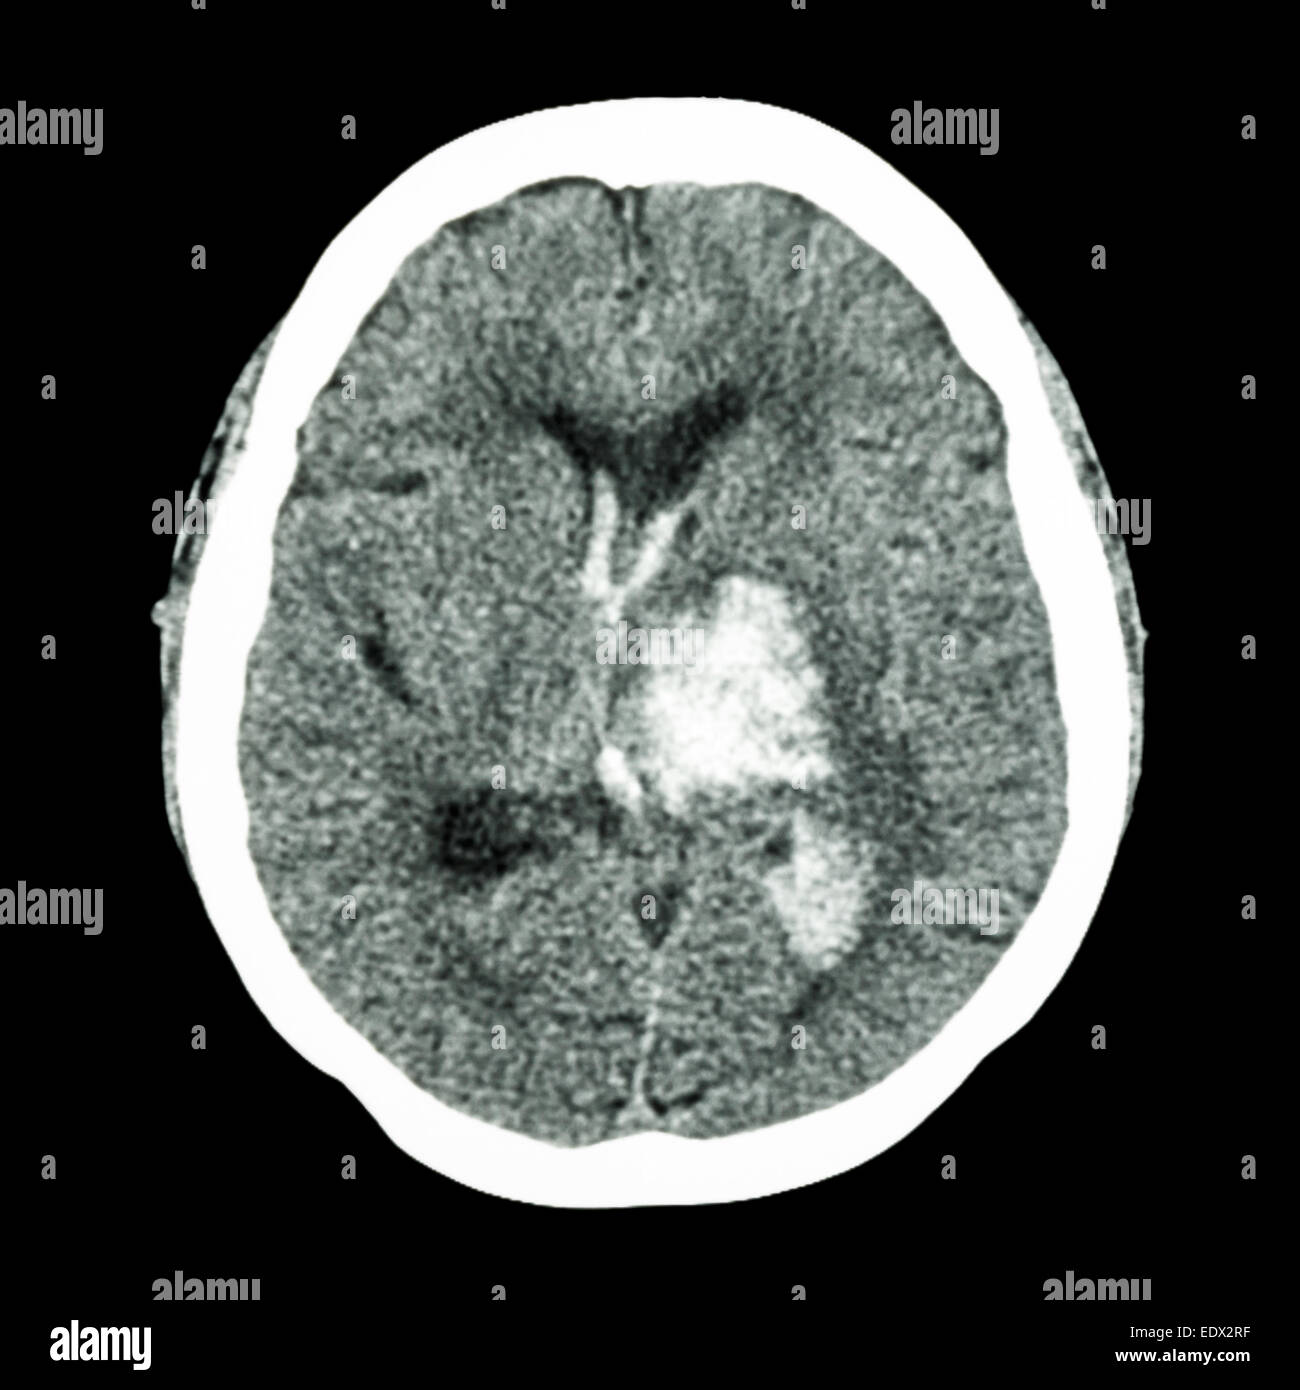

Computed tomography image of the patient 14 days after stroke onset Thalamic Hemorrhage Stroke Clinical presentations of thalamic stroke fall into 4 principal vascular syndromes (paramedian, tuberothalamic, inferolateral, and posterior choroidal arteries),. A blood clot blocking off blood flow (ischemic) or bleeding of a blood vessel in the. A thalamic stroke occurs when an artery that supplies blood to the thalamic area is blocked or ruptures. Ischemic strokes happen when small blood vessels become. Thalamic Hemorrhage Stroke.

Computed tomography showing left thalamus hemorrhage (axial view Thalamic Hemorrhage Stroke A blood clot blocking off blood flow (ischemic) or bleeding of a blood vessel in the. Ischemic strokes happen when small blood vessels become blocked. There are two different causes of strokes: Clinical presentations of thalamic stroke fall into 4 principal vascular syndromes (paramedian, tuberothalamic, inferolateral, and posterior choroidal arteries),. Treating a thalamic stroke is focused on prompt treatment of. Thalamic Hemorrhage Stroke.

CT brain show left thalamic hemorrhage (Hemorrhagic stroke Stock Thalamic Hemorrhage Stroke Thalamic strokes can be ischemic or hemorrhagic: Clinical presentations of thalamic stroke fall into 4 principal vascular syndromes (paramedian, tuberothalamic, inferolateral, and posterior choroidal arteries),. Treating a thalamic stroke is focused on prompt treatment of the underlying cause of the stroke in combination with extensive rehabilitation and therapy to promote recovery. The thalamus is located nearly in the center of. Thalamic Hemorrhage Stroke.

Plain axial CT scan, showed left thalamic hemorrhage wi Openi Thalamic Hemorrhage Stroke Clinical presentations of thalamic stroke fall into 4 principal vascular syndromes (paramedian, tuberothalamic, inferolateral, and posterior choroidal arteries),. Hemorrhagic strokes occur when there is bleeding in. Treating a thalamic stroke is focused on prompt treatment of the underlying cause of the stroke in combination with extensive rehabilitation and therapy to promote recovery. Ischemic strokes happen when small blood vessels become. Thalamic Hemorrhage Stroke.